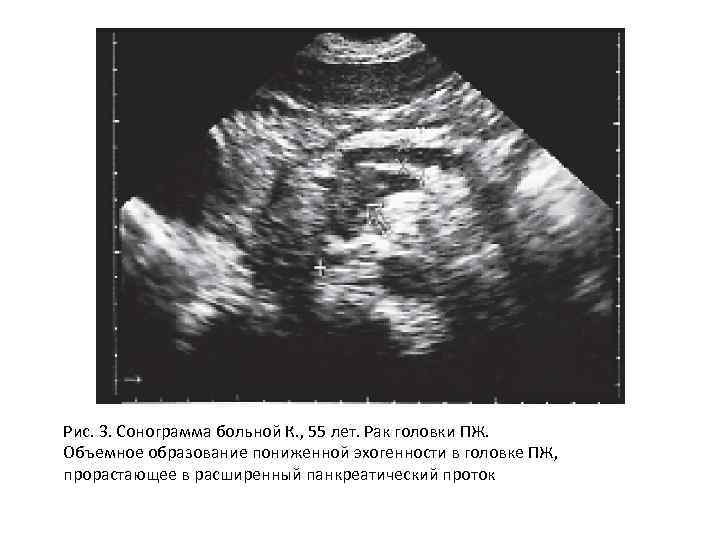

Рис. 3. Сонограмма больной К. , 55 лет. Рак головки ПЖ. Объемное образование пониженной эхогенности в головке ПЖ, прорастающее в расширенный панкреатический проток